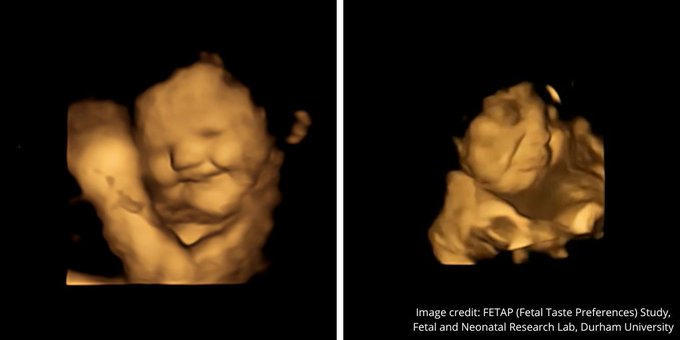

Τα έμβρυα παίρνουν πιο «γελαστό πρόσωπο» στη μήτρα όταν εκτίθενται στη γεύση των καρότων που καταναλώνει η μητέρα τους και «πιο θλιμμένη έκφραση» όταν εκτίθενται στη λαχανίδα (κέιλ), σύμφωνα με μελέτη που δημοσιεύθηκε στο περιοδικό Psychological Science.

Αφού περίμεναν 20 λεπτά μετά την κατανάλωση, οι γυναίκες υποβλήθηκαν σε 4D υπερηχογραφήματα, τα οποία συγκρίθηκαν με 2D εικόνες των εμβρύων.

Το τράβηγμα της γωνίας των χειλιών, που υποδηλώνει χαμόγελο ή γέλιο, ήταν σημαντικά υψηλότερο στην ομάδα του καρότου σε σύγκριση με την ομάδα της λαχανίδας και την ομάδα ελέγχου. Ενώ κινήσεις όπως η ανύψωση του άνω χείλους, η ρίψη του κάτω χείλους προς τα κάτω, το πάτημα των χειλιών και ένας συνδυασμός αυτών – που υποδηλώνει ένα πρόσωπο που κλαίει – ήταν πολύ πιο συχνές στην ομάδα της λαχανίδας σε σχέση με τις άλλες ομάδες.